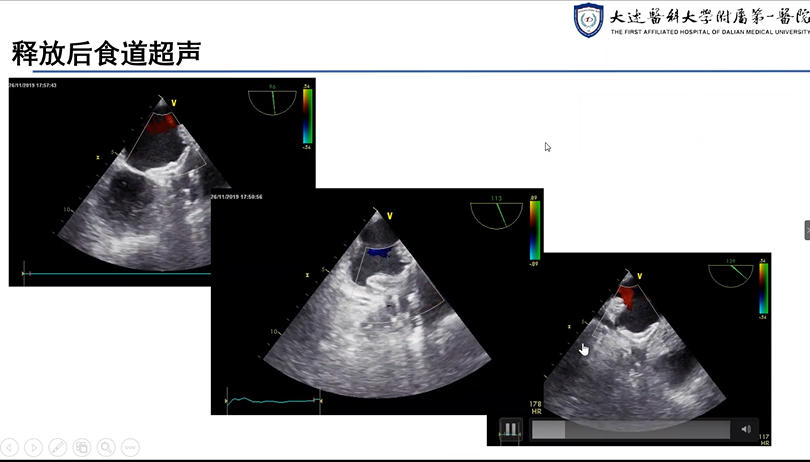

大连医科大学附属第一医院肖宪杰教授分享了两例使用LAmbre™左心耳封堵器系统进行的挑战性案例,并将其对于术中造影时如何排除残存空气以及如何应对常规体位造影成形不佳等问题的解决方案与专家们进行了充分探讨。